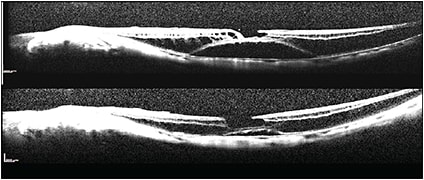

Figure 3. Pre- and postoperative OCT scans of myopic schisis at four months. At nine months the schisis was fully repaired. The initial acuity was 20/70-, and the final was 20/50-.